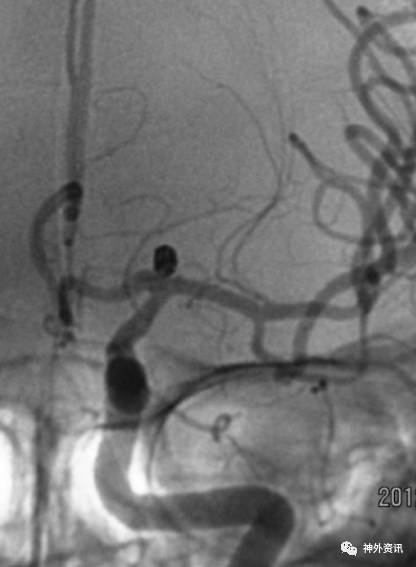

病例一

病例二

病例三